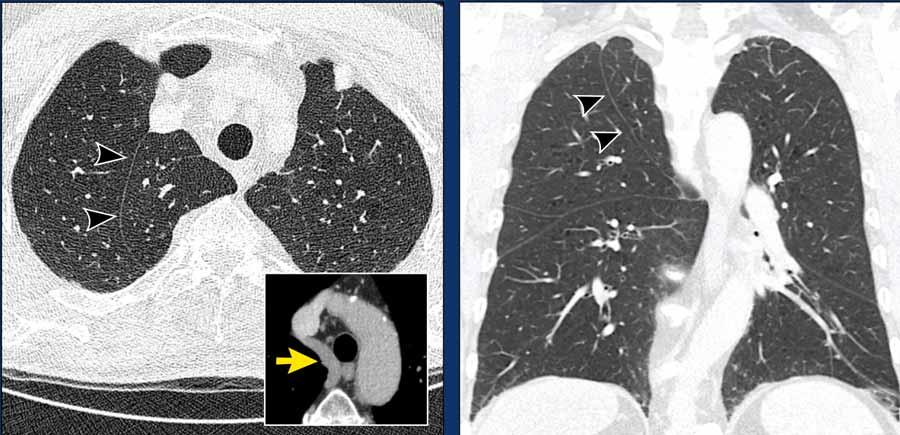

Hình ảnh

Thùy azygos ở nam giới 74 tuổi với tĩnh mạch azygos ở vị trí bình thường (mũi tên vàng).

Đây là một trường hợp khác, trong đó tĩnh mạch azygos đi qua rãnh liên thùy azygos (đầu mũi tên).